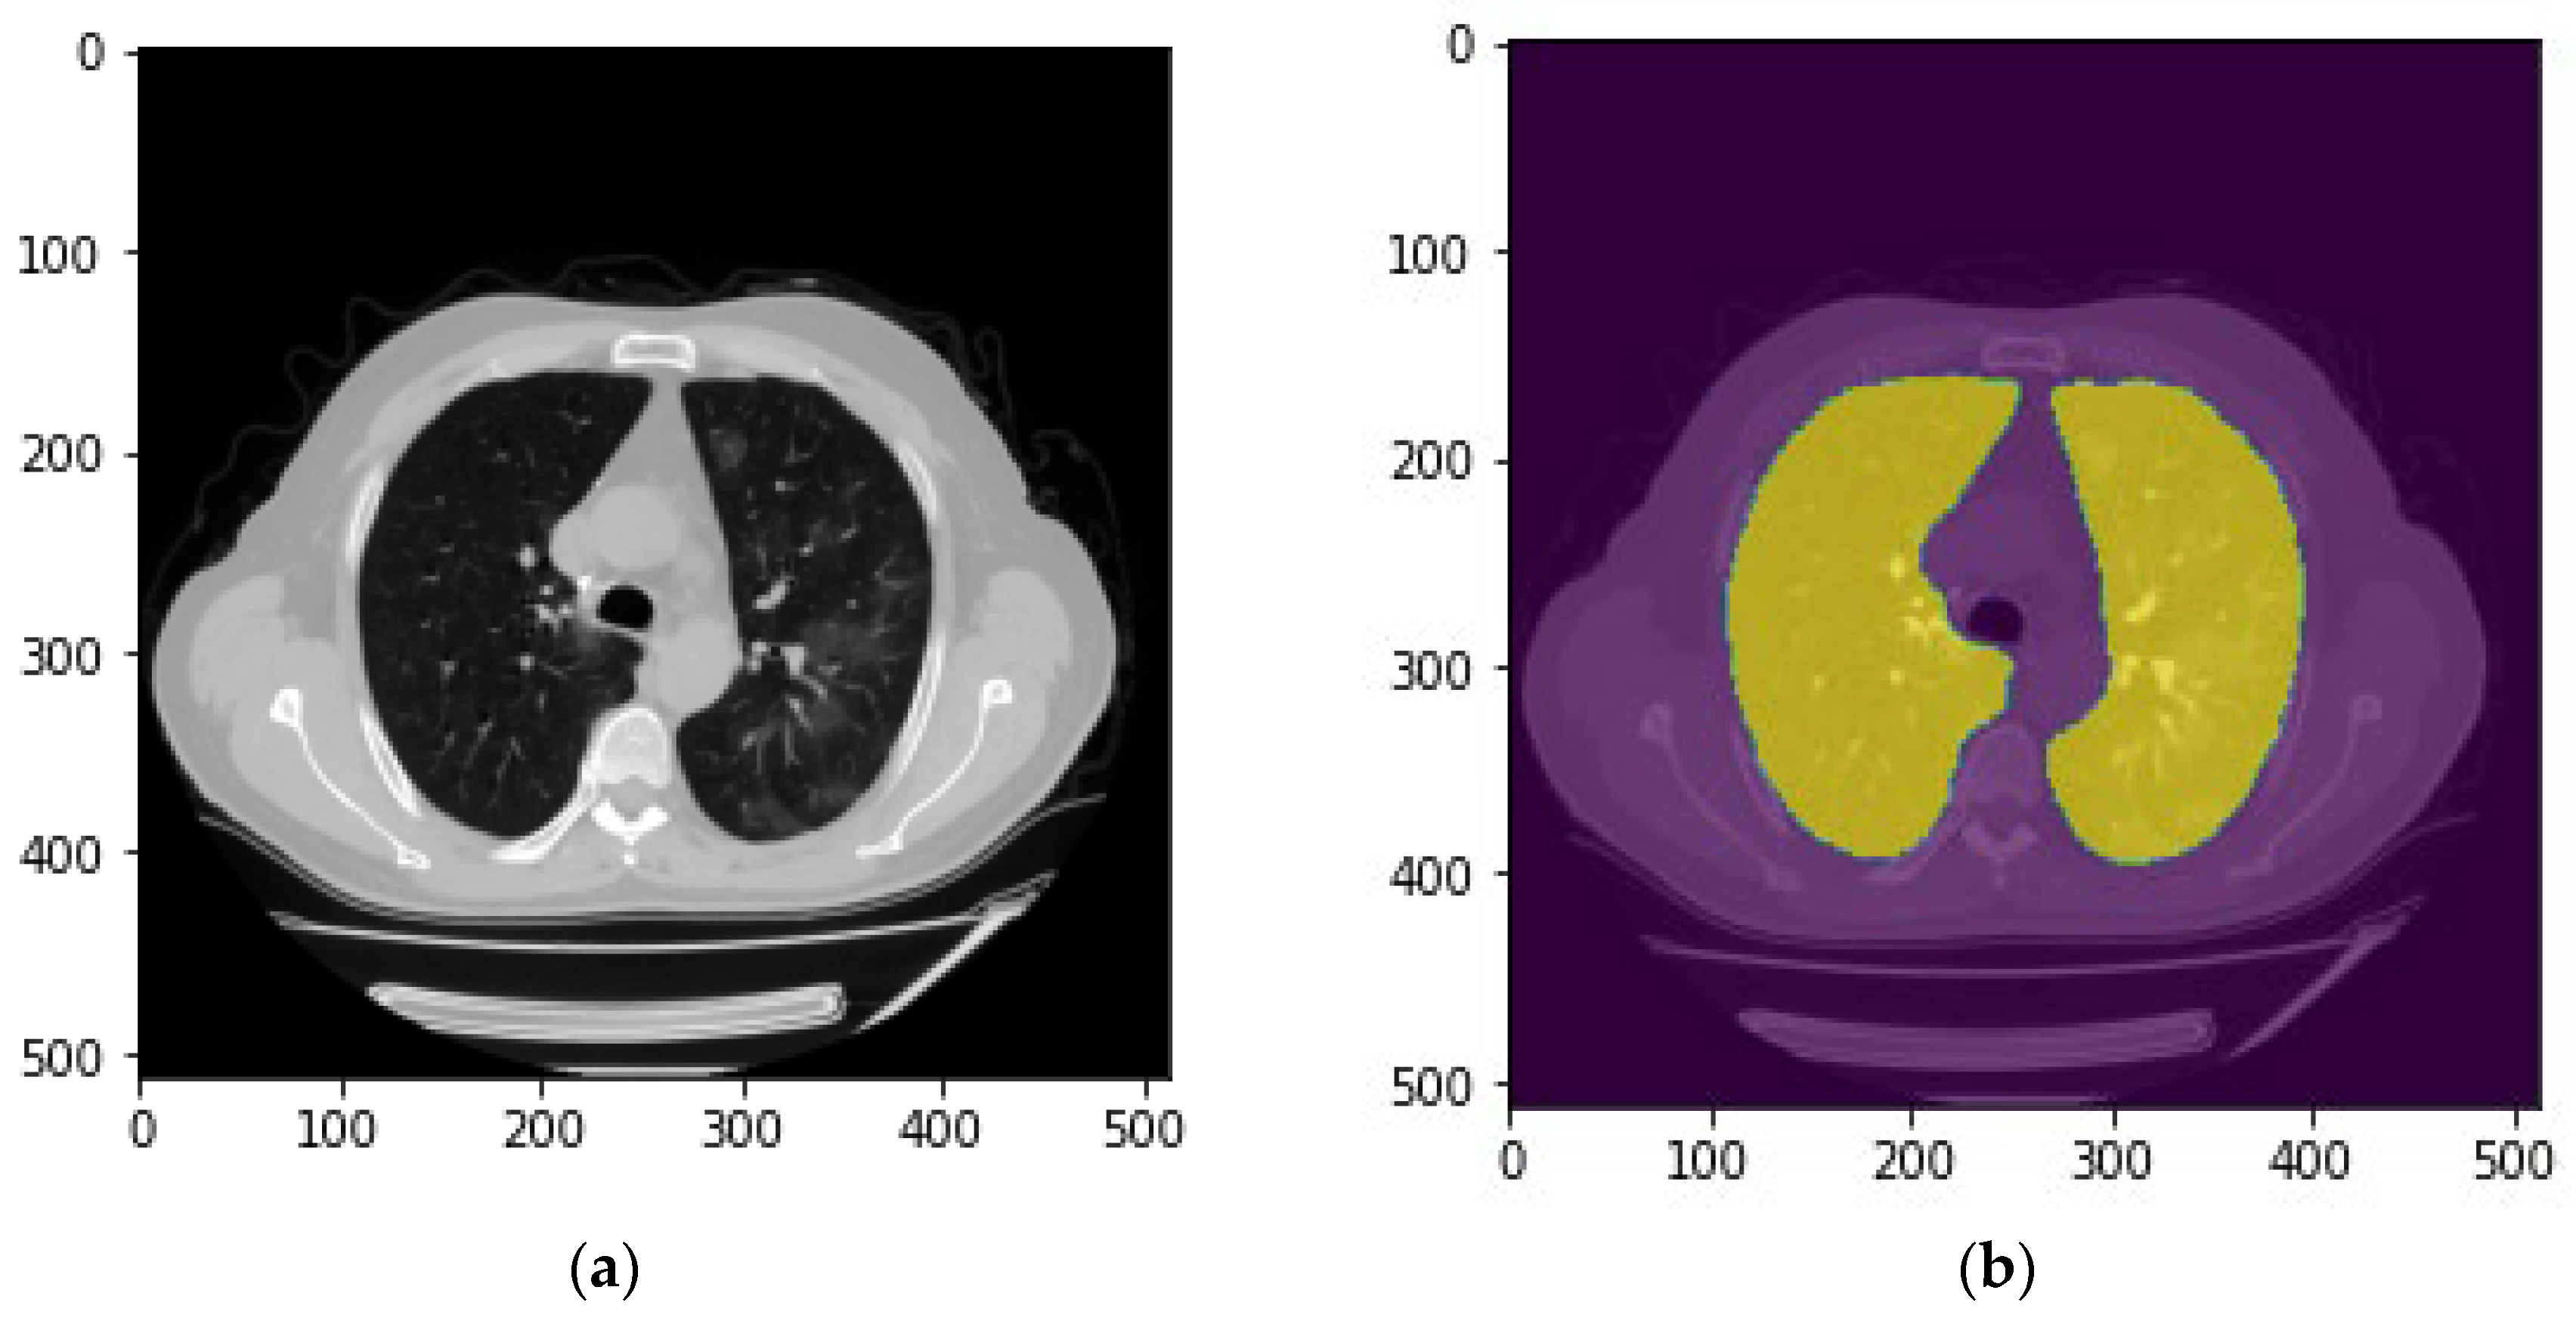

The first step is to segment lung area depicting on each CT slide. For this purpose, a publicly available model for lung parenchyma segmentation was used to create lung masks and segmenting the lung area [21]. In brief, this model used the U-net with the only adaption being batch normalization after each layer. Figure 3 demonstrates an example of the created lung mask and the lung segmentation result using this mask.

Figure 3. An example of the lung segmentation. (a) Raw CT image; (b) CT image and lung mask.